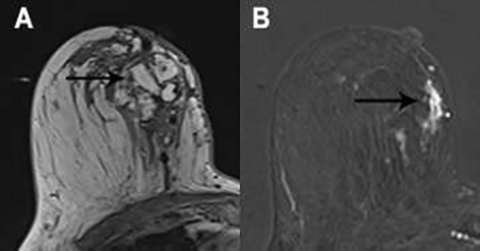

The normal appearance following mastectomy is dependent on the type of reconstruction techniques include autologous tissue flaps and implant reconstruction. Autologous tissue flaps include the transverse abdominis myocutaneous (TRAM) and deep inferior epigastric perforator (DIEP) flaps, although numerous other techniques exist. In general, post-surgical changes such as seromas and fat necrosis will also be encountered following mastectomy as in breast conservation surgery. Recurrences are most common in the anterolateral breast and axilla, where residual breast tissue may remain (Figure 6)6,7

Figure 6: T1-weighted post contrast image with fat saturation. Previous mastectomy with implant reconstruction. Enhancing masses are seen in the axilla and in the anterior breast, the latter of which extends to the nipple-areolar complex. Biopsy demonstrated recurrent breast cancer.